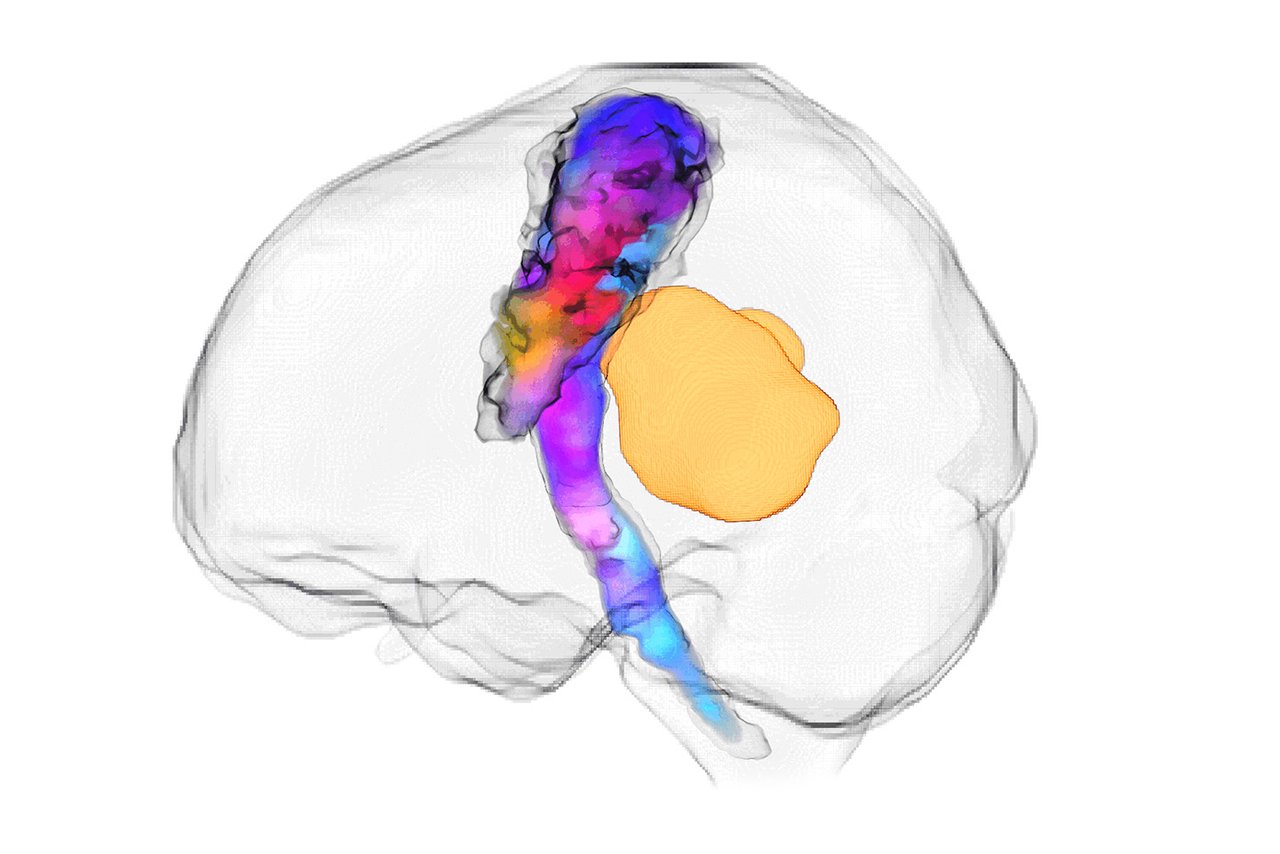

GOSH Staff Network’s favourite: Stimulating the brain, an evolving treatment for children with drug-resistant seizures

Entered by Rory Piper, Lewis Spitz Surgeon Scientist PhD Student, this image resembling the features of a lion has captured the cross-section of a simulated brain used to help study potential treatments for epilepsy in children.

Deep brain stimulation (DBS) is a type of brain surgery that uses electrical pulses to change the way the brain works. This treatment can be helpful in certain brain conditions, such as epilepsy, in which the brain's electrical activity is abnormal and needs to be corrected or changed. Here, a representative cross-section of the brain (looking from front to back) shows two DBS wires implanted in the thalamic regions (blue), which are parts of the brain involved in the routing of electrical signals.